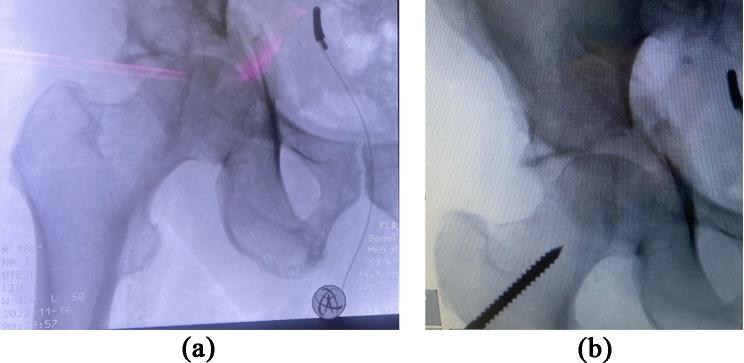

机器人辅助髋臼前柱钢板固定术——一种新技术的临床描述

Robotic-assisted plate fixation of the anterior acetabulum - clinical description of a new technique.

We present a detailed procedure for the robotic-assisted plate osteosynthesis of an anterior acetabular fracture. The purpose of this work was to describe a robotic-assisted minimally invasive technique as a possible method for reducing complications, pain, and hospitalization. Another goal was to present technical recommendations and to assess potential pitfalls and problems of the new surgical approach.

METHODS

Surgery was performed in an interdisciplinary setting by an experienced orthopedic surgeon and a urologist. The DaVinci System with standard instruments was used. Reduction was achieved through indirect traction of a pin that was introduced into the femoral neck and direct manipulation via the plate. The plate position and fixation were achieved through 7 additional minimally invasive incisions.

RESULTS

The technique has multiple advantages, such as no detachment of the rectus abdominal muscle, a small skin incision, and minimal blood loss. Furthermore, this approach might lower the incidence of hernia formation, infection, and postoperative pain.

我们介绍一种用于髋臼前柱骨折机器人辅助钢板内固定的详细手术步骤。这项工作的目的是描述一种机器人辅助的微创技术,作为减少并发症、疼痛和住院时间的一种可能方法。另一个目标是提出技术建议,并评估这种新手术方法的潜在陷阱和问题。

手术在多学科环境下由一位经验丰富的骨科医生和一位泌尿科医生进行。使用配备标准器械的达芬奇系统。通过将一根针插入股骨颈进行间接牵引,并通过钢板进行直接操作来实现复位。通过另外7个微创切口来实现钢板的定位和固定。

结果